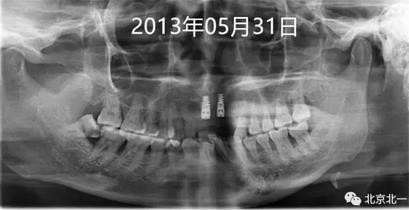

圖八:三年后因牙冠松動脫離復(fù)診, 三年期間沒有復(fù)診。

圖十、圖十一:2013年到2016年比較X片,骨平面很穩(wěn)定。牙齦及牙周黏膜健康,區(qū)別在于2016年時候31牙位缺失。